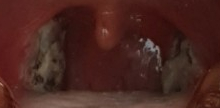

다음날부터 계속 사진 괴롭히기 주의

보시면 아시겠지만, 경사가 떨어지고 나서 없어진 편도선이 눈에 띄기 시작합니다.하도 밥을 잘 먹어서 경사는 언제 떨어졌는지 모르게 떨어졌어요.

2주 정도 지나면 배나 떨어진 후에는 아무렇지도 않아요. ㅎㅎㅎ